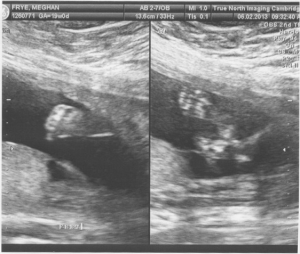

We got our first look at our little French Frye at the True North in Cambridge today. After a very thorough ultrasound, they brought Erik in for our first peek. First she showed us the head and face, little arms and legs. Then the money shot – saw a little bum and oh, what is that little protrusion? All I could squeak out was “is that a little penis?!?!”. Reliving the story later this evening, Erik and I both realized she actuallydidn’t answer… but yeah – it’s a boy!! Erik always said he would be happy either way – but I was ecstatic to learn we are having a boy (I’m sure I would’ve been fine with a girl too, but now I know my baby won’t be wearing pink! Hurray!).